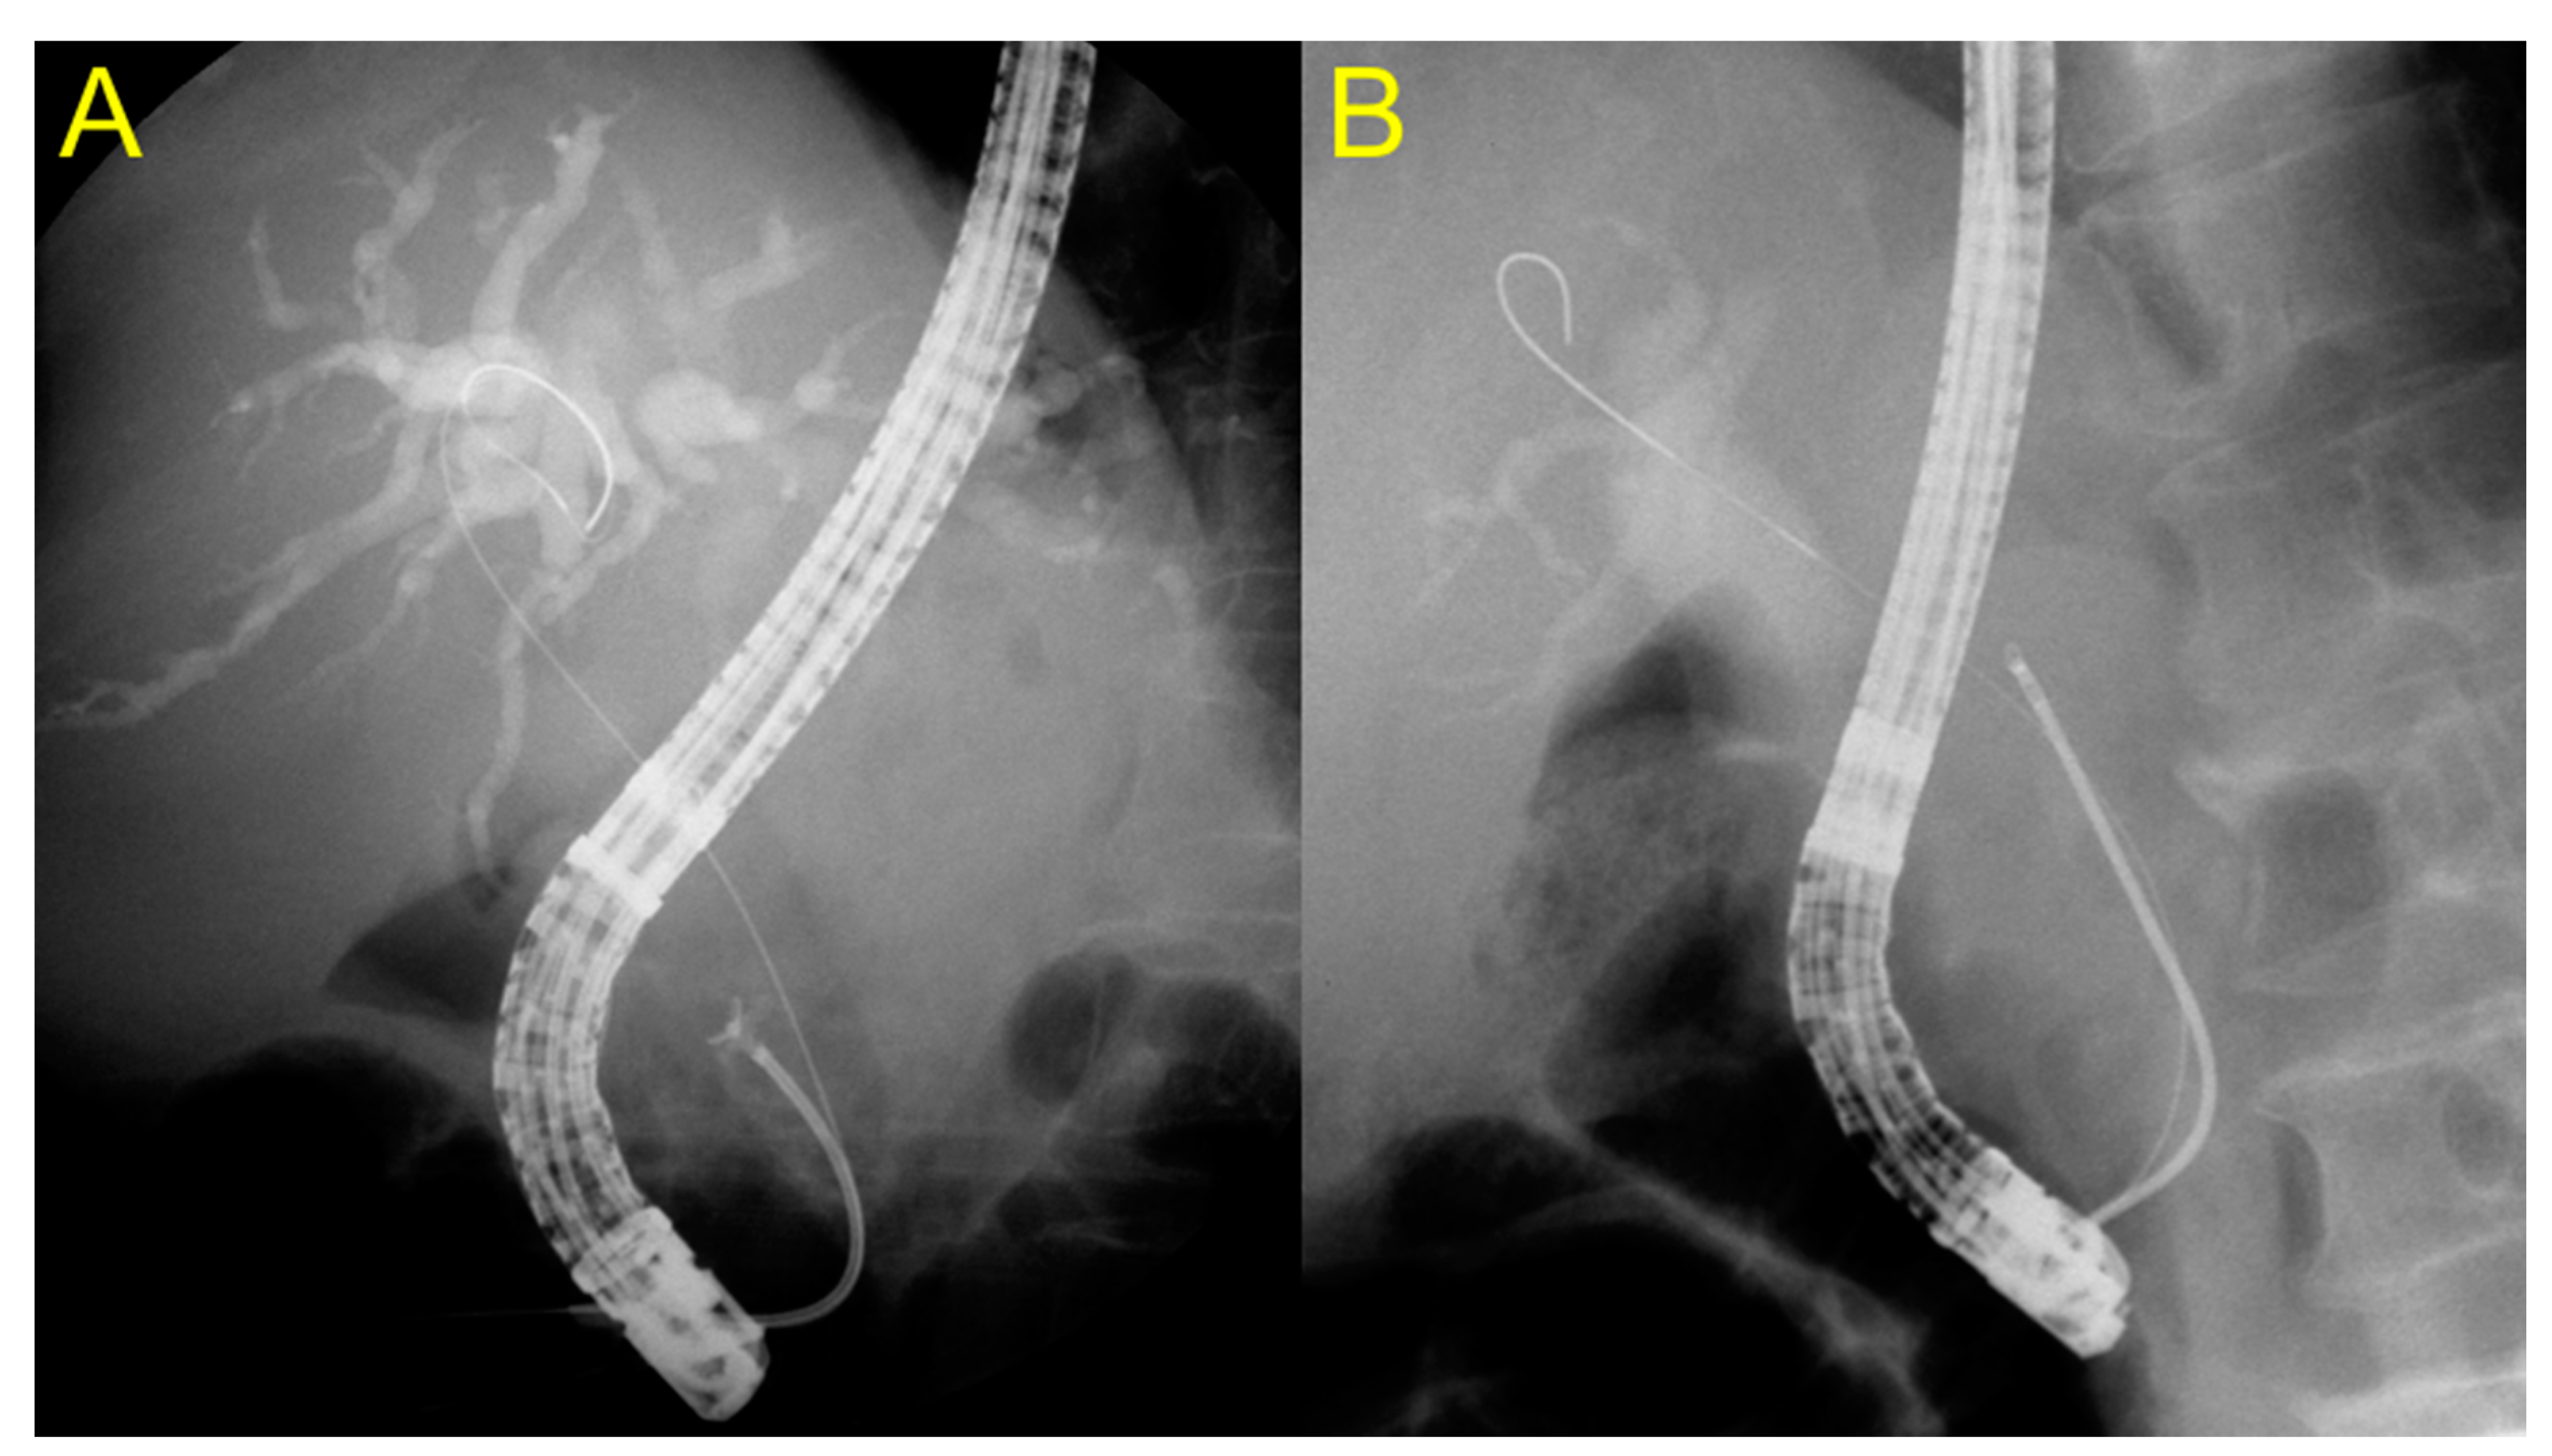

2.3. Endoscopic Procedures for ERCP